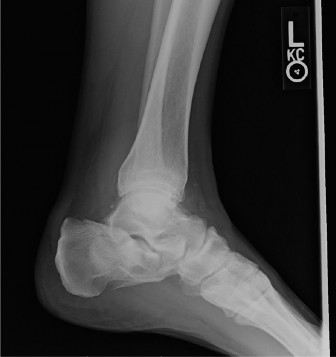

A 26-year-old man sustained an injury to his right ankle when he was caught in an avalanche while snowboardin…